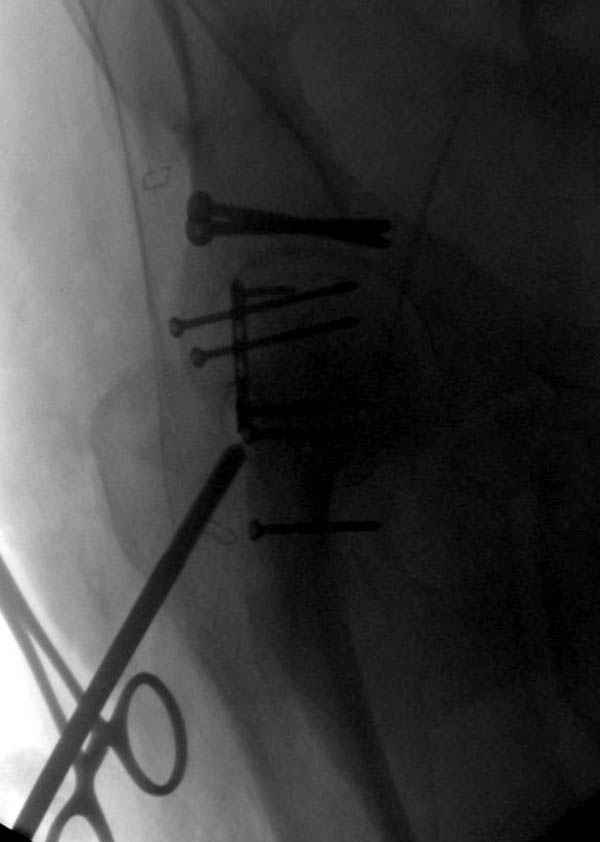

Второй случай, для лечения перелома проксимального

плеча применили пластину "Hand Innovation"

http://www.handinnovations.com/pdf/S3_technique.pdf

Пластина имеет преимущества перед другими "Locking

Implants", потому что пластину можно уложить намного ниже чем другие пластины и имеется возможности проведения шурупов под 130 градусным углом, таким образом можно уменьшить операционный разрез в проксимальной части.

Из-за большого обьема конечности доступ к бугорку был затруднен, предварительно зафиксированный шуруп не удержал бугорок, поэтому фиксацию провели толстыми нитками. Состоятельность фиксации бугорка обычно проверяем во время операции, под рентген контролем проводится движения конечности, особенно приведение.